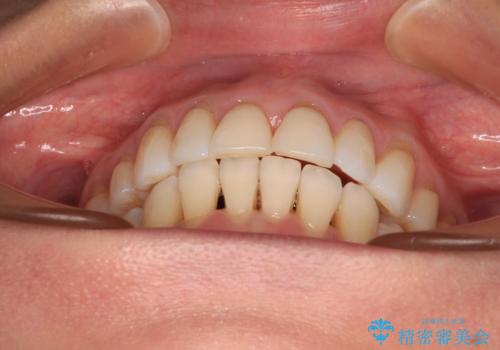

後戻りで突出した口元を引っ込めたい インビザライン矯正治療

- 上の前歯の出っ歯を治したいとのことで来院された患者様です。

後戻りによる再矯正というもともあり、インビザラインを希望されていました。

上顎の歯は後方移動とIPR(歯と歯の間を削る)によって口元が引っ込むように、下顎は歯列全体の拡大とIPRによって上顎とバランスよく咬み合うように設計し、インビザラインにより治療を行うこととしました。

治療を開始して暫くして、勤務先から2年以上帰国することができず、それまでの移動がほとんど後戻りしてしまい、帰国後に再度後戻りをリカバリーするための治療を行うこととなりました。

5年以上の治療期間がかかりましたが、気になっている部分を改善することができました。